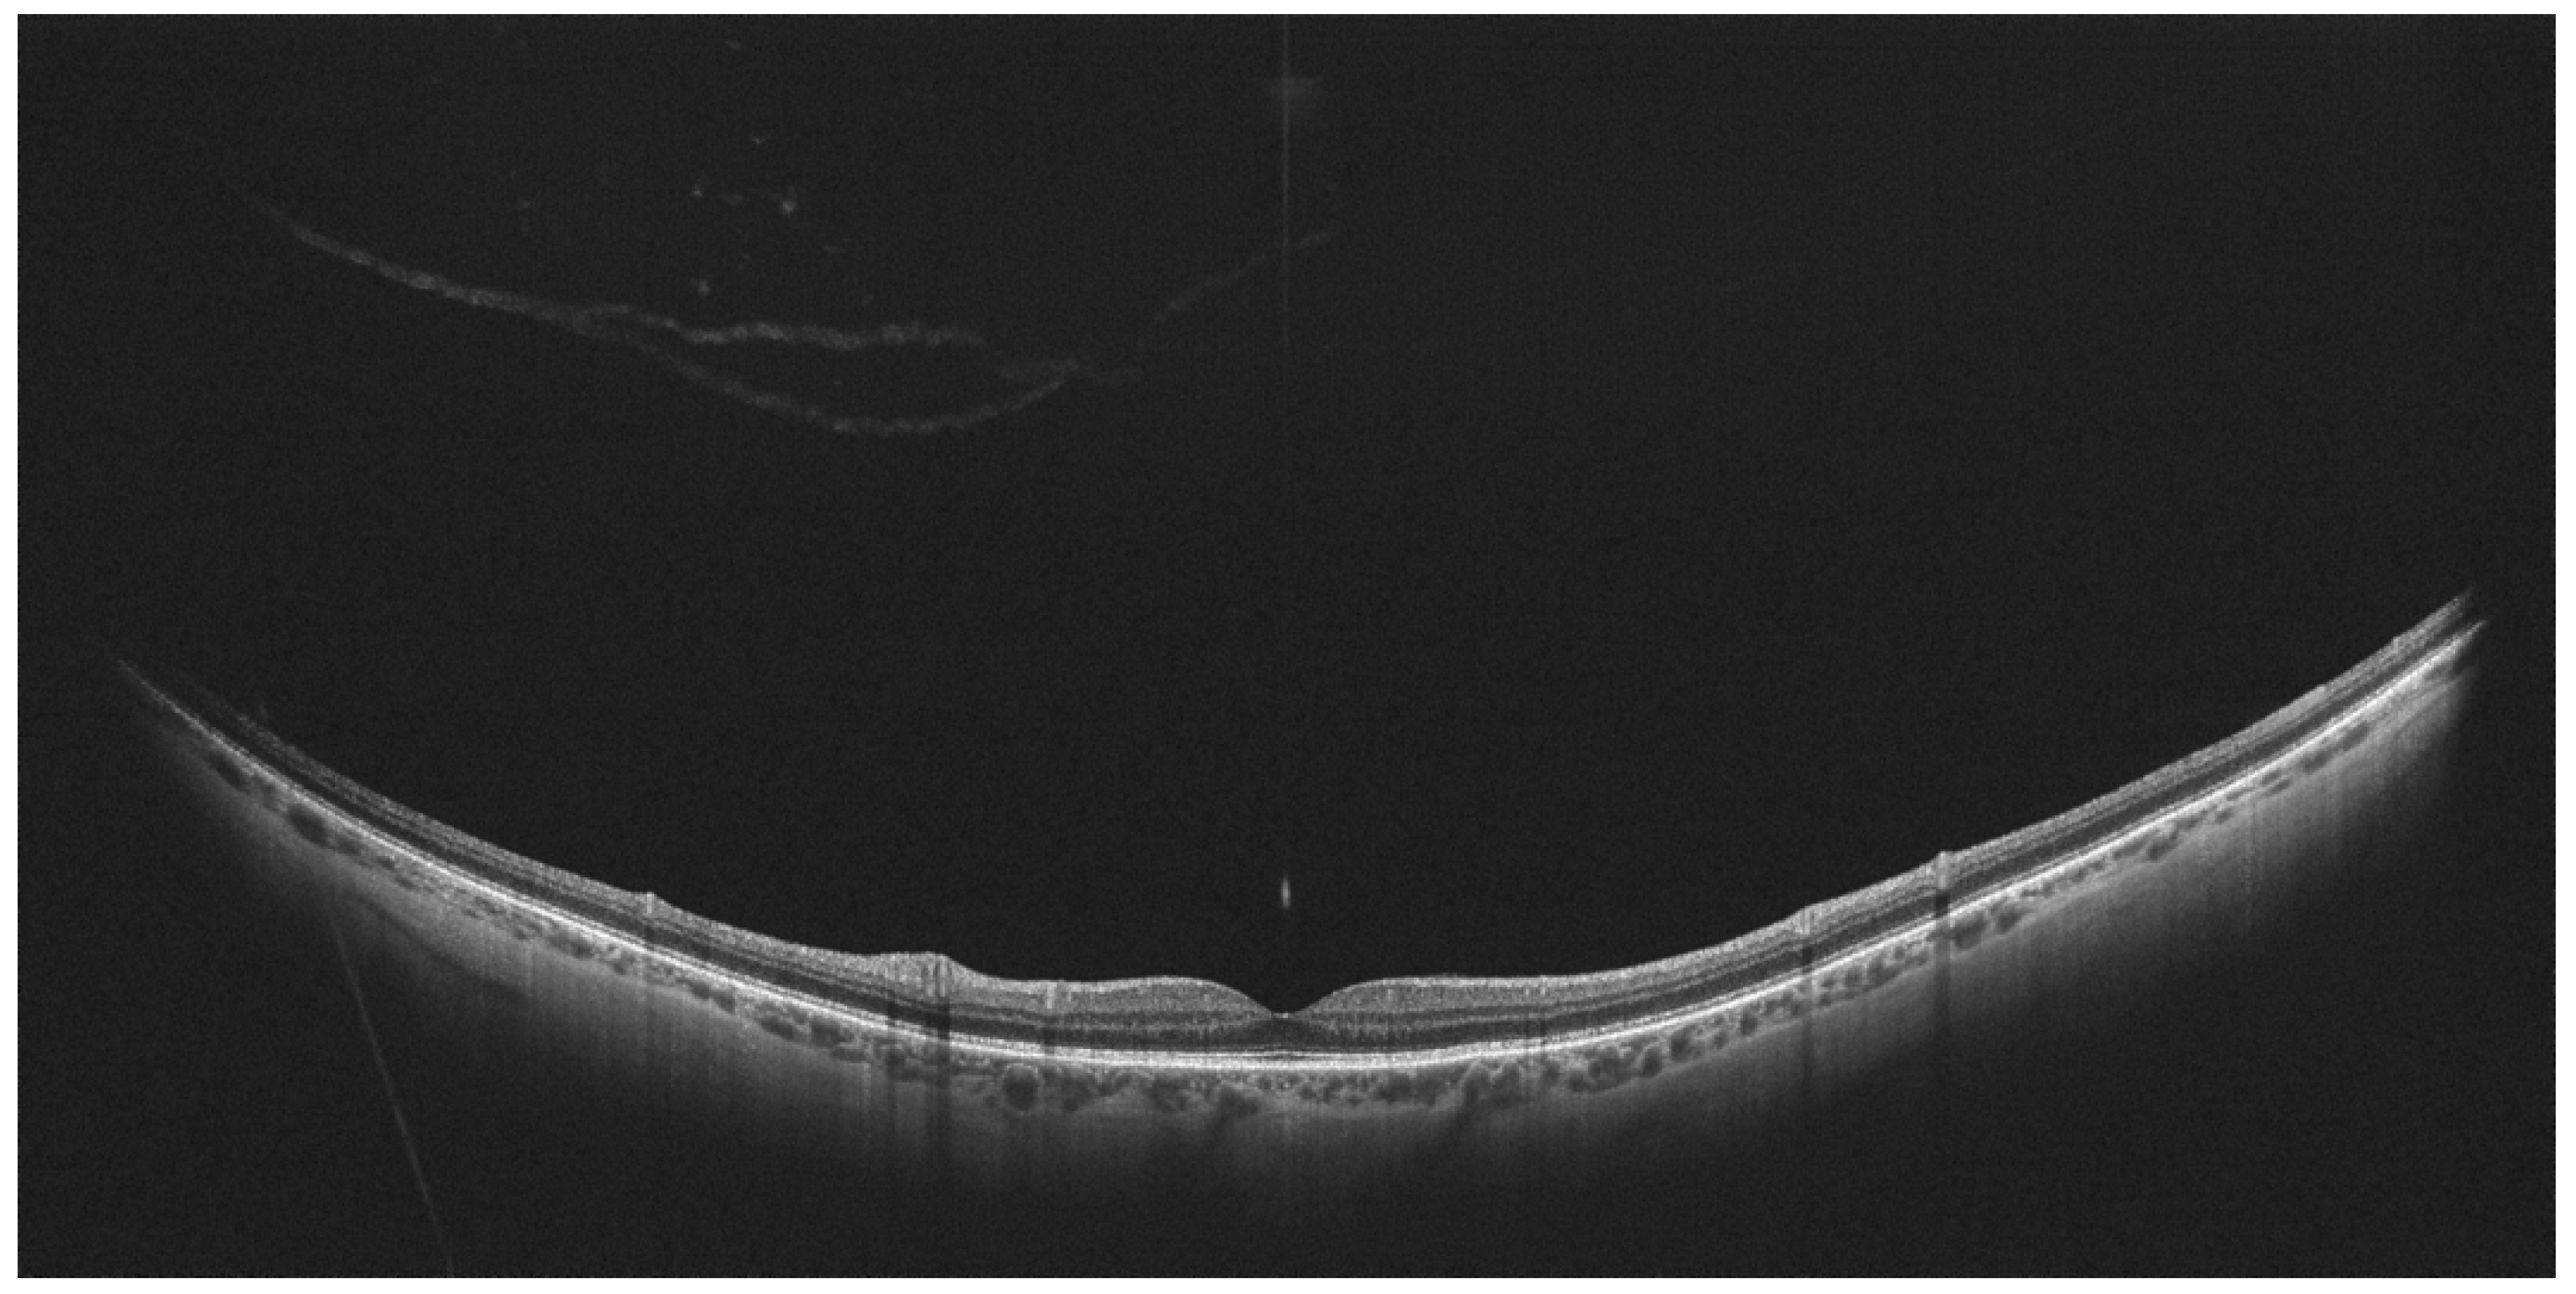

- Govetto, A.; Sebag, J.; Lucchini, S.; Ballabio, C.; Matteucci, M.; Ranno, S.; Carini, E.; Virgili, G.; Bacherini, D.; Radice, P. Imaging rhegmatogenous retinal lesions and peripheral vitreo-retinal interface with wide-field optical coherence tomography. Retina 2023, 44, 269–279. [Google Scholar] [CrossRef] [PubMed]

- Kurobe, R.; Hirano, Y.; Ogura, S.; Yasukawa, T.; Ogura, Y. Ultra-Widefield Swept-Source Optical Coherence Tomography Findings of Peripheral Retinal Degenerations and Breaks. Clin. Ophthalmol. 2021, 15, 4739–4745. [Google Scholar] [CrossRef] [PubMed]

- Tsukahara, M.; Mori, K.; Gehlbach, P.L.; Mori, K. Posterior Vitreous Detachment as Observed by Wide-Angle OCT Imaging. Ophthalmology 2018, 125, 1372–1383. [Google Scholar] [CrossRef] [PubMed]